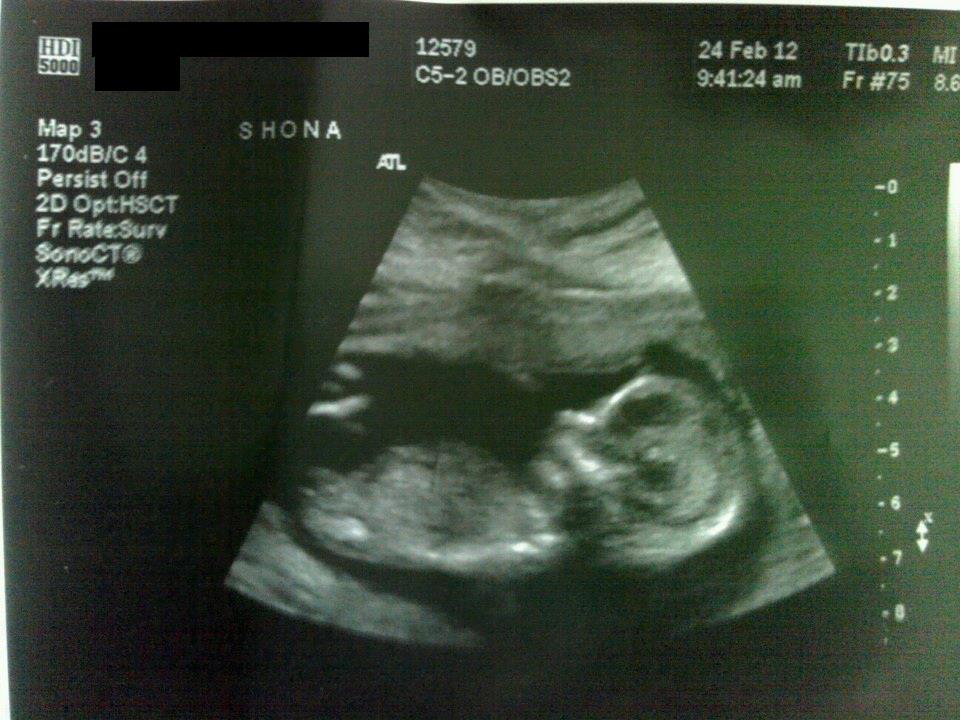

and 13w4day (right of photo = my left, left of photo = my right)

Attachment 1935

please tell me what my chances are of hearing boy or girl in %... and please do not give me the 50/50 spiel.